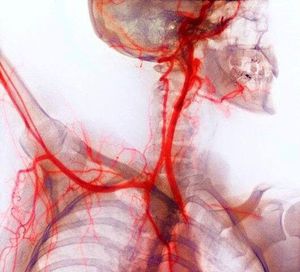

The bones (purple) are also seen on the X-ray, aiding identification of the arteries.The head (upper right) has been turned to one side to expose the right-hand side of the neck and its carotid arteries (internal and external). These arteries bring oxygenated blood to the head. The right arm (centre left) has been raised to show how the subclavian artery passes under the collar bone (clavicle) and into the arm. The arteries carry oxygenated blood from the heart (not seen). The arteries have been highlighted arteriographically by injecting them with a radio-opaque dye, creating a medium to absorb the X-rays.